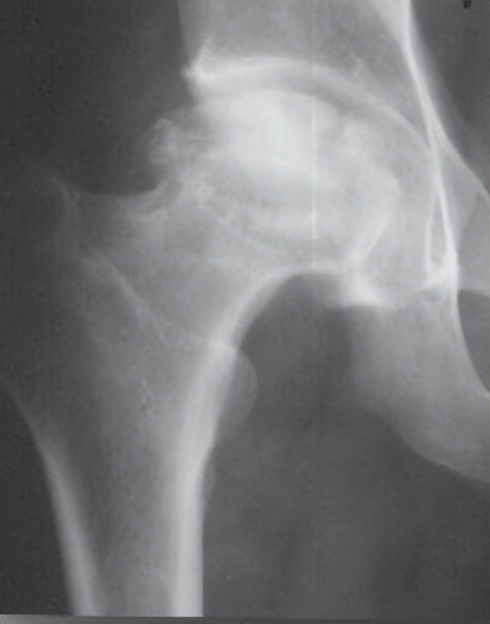

股骨头坏死是由于股骨头血供中断或受损,引起骨细胞及骨髓成分死亡,继而导致股骨头结构改变,股骨头塌陷,关节毁损,引起患者疼痛,髋关节功能障碍的疾病,是目前骨科领域常见的难治性疾病。该病好发于中青年,常见病因是糖皮质激素的过度使用、长期酗酒以及髋部外伤导致股骨头血供中断。股骨头坏死一旦发生,如不及时处理,后期常需要进行人工关节置换。

坏死股骨头

正常股骨头